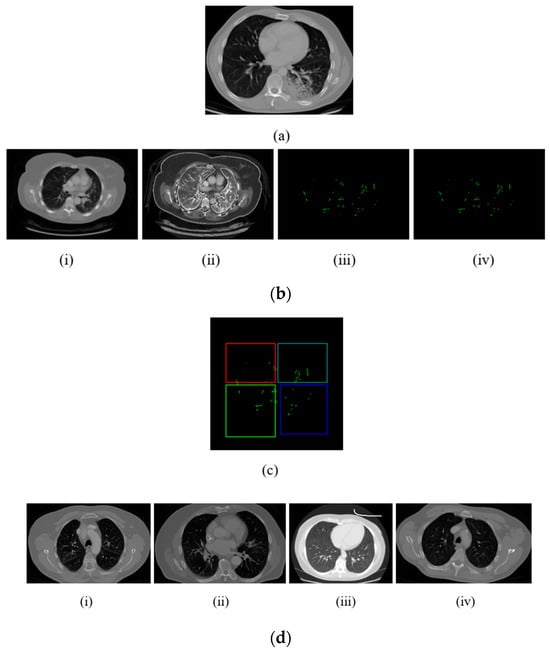

- Preprocessing: To enhance image quality and make additional analysis easier, lung computed tomography images are first preprocessed. This involves multiple steps.

- Noise Reduction: We remove noise from CT images by applying a sophisticated improved anisotropic diffusion filter (I-ADF) approach.

- Contrast stretching: Enhancing the contrast of the images makes important features more distinguishable.

- Convex Hull Lung Region Extraction: In order to concentrate the analysis on the pertinent area, we isolate the lung region.

- Edge Enhancement: Using the unsharp masking filter (UMF) improves the ability to define the image edges.

- Segmentation: The Bates distribution coati optimization (B-RGS) algorithm segments the preprocessed pictures for feature extraction. Important elements that are essential for precise categorization are removed from the segmented images.

- Classification: The images are categorized as either normal or abnormal using the PResNet classifier. If the output is abnormal, thorough risk screening is carried out to ascertain whether the cancer risk is low or high. This multi-step process guarantees a complete evaluation with precise predictions.

3.1. Preprocessing

3.2. Segmentation

3.3. Feature Extraction